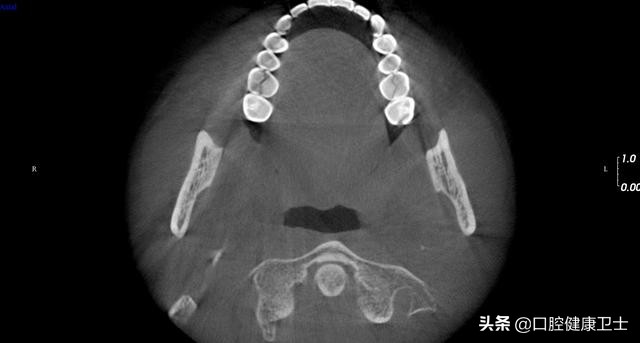

CT见,右上第一磨牙近远中向劈裂,左上第一磨牙也是近远中向劈裂,暂不处理。